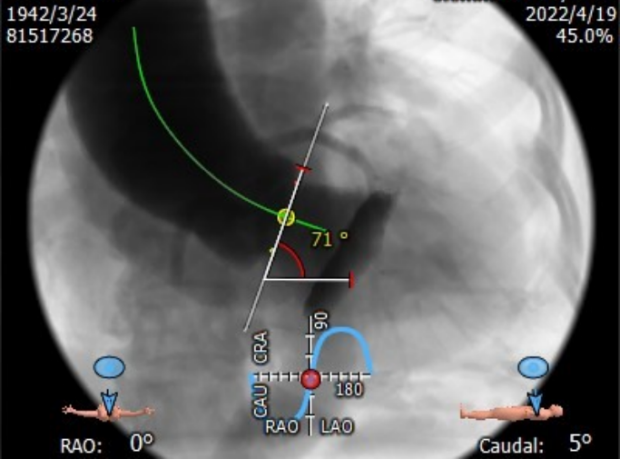

升主动脉扩张,平均周长径48.3mm,主动脉瓣环与水平面夹角71°,主动脉弓角与弓距可。

球囊预扩角度LAO 2°,CRA 1°(左冠切线位),跨瓣和释放角度RAO 16°,CAU 36°(左右重合),释放瓣膜后观察瓣架形态,造影确认瓣周漏和反流情况。